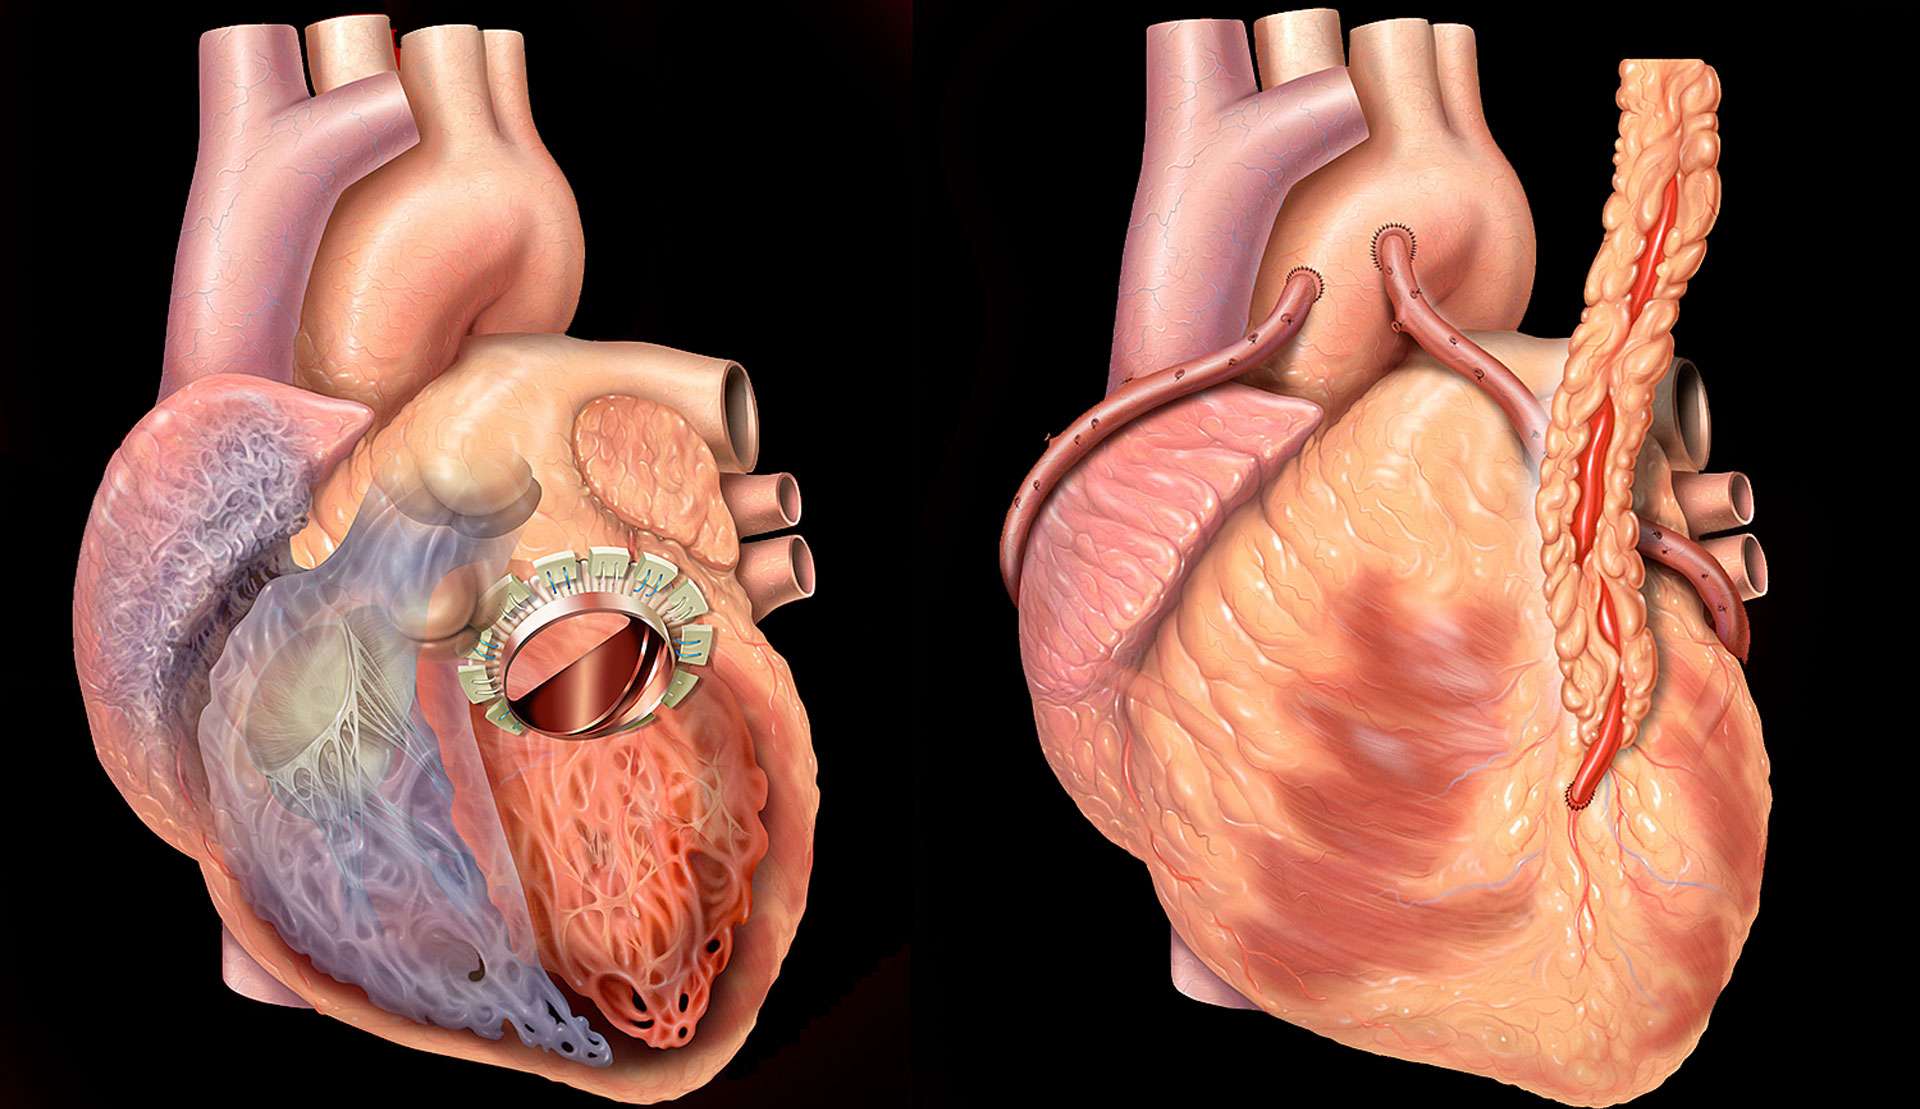

Пороки сердечно-сосудистой системы: виды и признаки